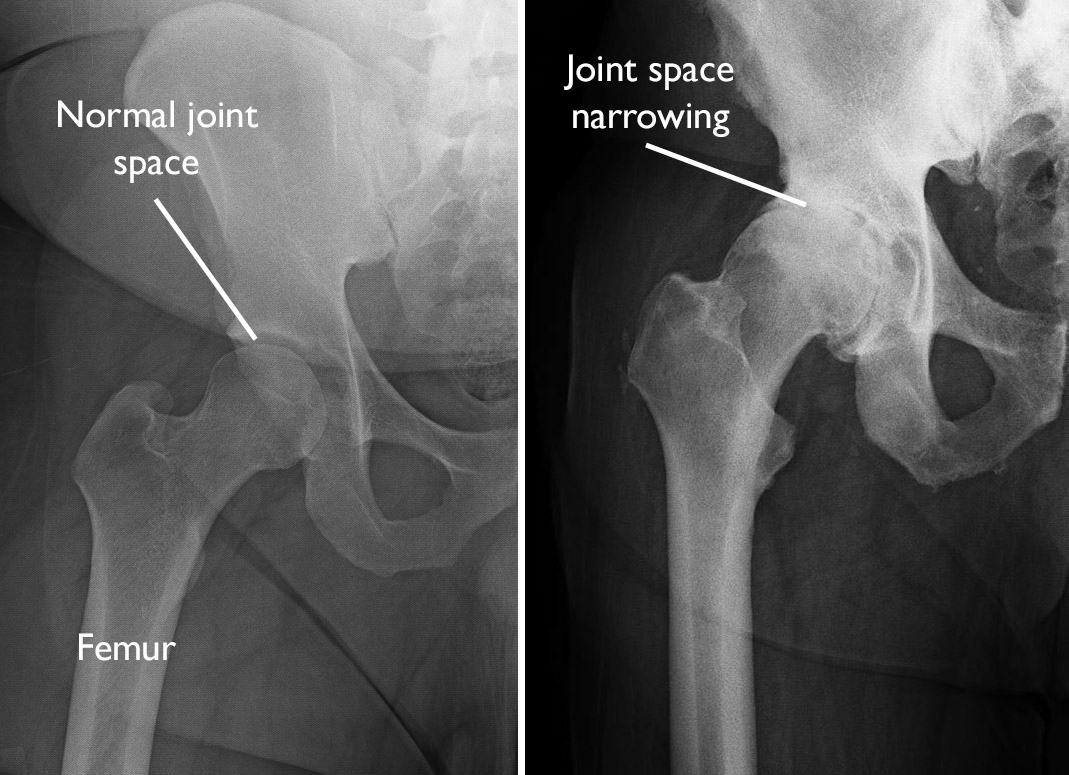

Arthritis is diagnosed through a careful evaluation of symptoms and a physical examination. X-rays are important to show the extent of any damage to the joint.

Osteoarthritis is often more painful in joints that bear weight, such as the knee, hip, and spine. However, joints that are used extensively in work or sports, or joints that have been damaged by injury may also show signs of osteoarthritis.

In many cases, bone growths called spurs develop at the edges of osteoarthritic joints. The bone can become harder (sclerosis). The joint becomes inflamed, causing pain and swelling. Continued use of the joint is painful.